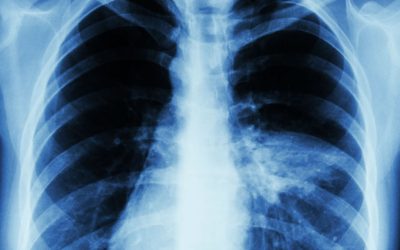

Алматы қалалық клиникалық ауруханасының пульмонолог дәрігері Ақжарқын Қалдыбек пневмонияның белгісіз белгілері туралы айтты. Оның айтуынша, пневмония кейде басқа аурулардың белгілерімен жасырын түрде өтуі мүмкін. Әдеттегі пневмония жөтелмен, қақырық шығарумен, жоғары температурамен және әлсіздікпен басталады. Бірақ атиптік пневмония қызу көтерілмей, бас және бұлшықет ауырсынуларымен, құрғақ жөтелмен немесе тамақтың ауруымен көрінуі мүмкін. Сондай-ақ кеуде қуысының невралгияға ұқсас…

Биыл Қазақстанда өкпе қабынуына шалдыққандардың саны айтарлықтай өскен. Денсаулық сақтау министрлігінің мәліметінше, алғашқы жартыжылдықта елімізде пневмонияның 49 мың 704 жағдайы тіркелген, деп хабарлайды Qazaq Today ақпарат агенттігі. Бұл былтырғы көрсеткішпен салыстырғанда 19,2 пайызға артық. Мамандар қалыптасқан жағдайды әлем бойынша омикрон штамының әлі де басымдық көрсетіп тұрғанымен байланыстырады. Ал көршілес Ресейде COVID-19 өршіді. Өткен аптада коронавирусқа шалдыққандардың…

Фото: depositphotos.com Қазақстанда пневмониямен ауыратындар санының айтарлықтай өскені тіркелді. Денсаулық сақтау министрлігі бұл Omicron штамының әртүрлі нұсқаларының таралуына байланысты ма деген сұраққа жауап берді. Ведомствоның мәліметінше, 2024 жылдың алғашқы алты айында Қазақстанда пневмонияның 49 704 жағдайы тіркелген, бұл өткен жылдың сәйкес кезеңімен салыстырғанда 19,2 пайызға артық. Салыстыру үшін, елде 2023 жылы пневмонияның 123 910 жағдайы…